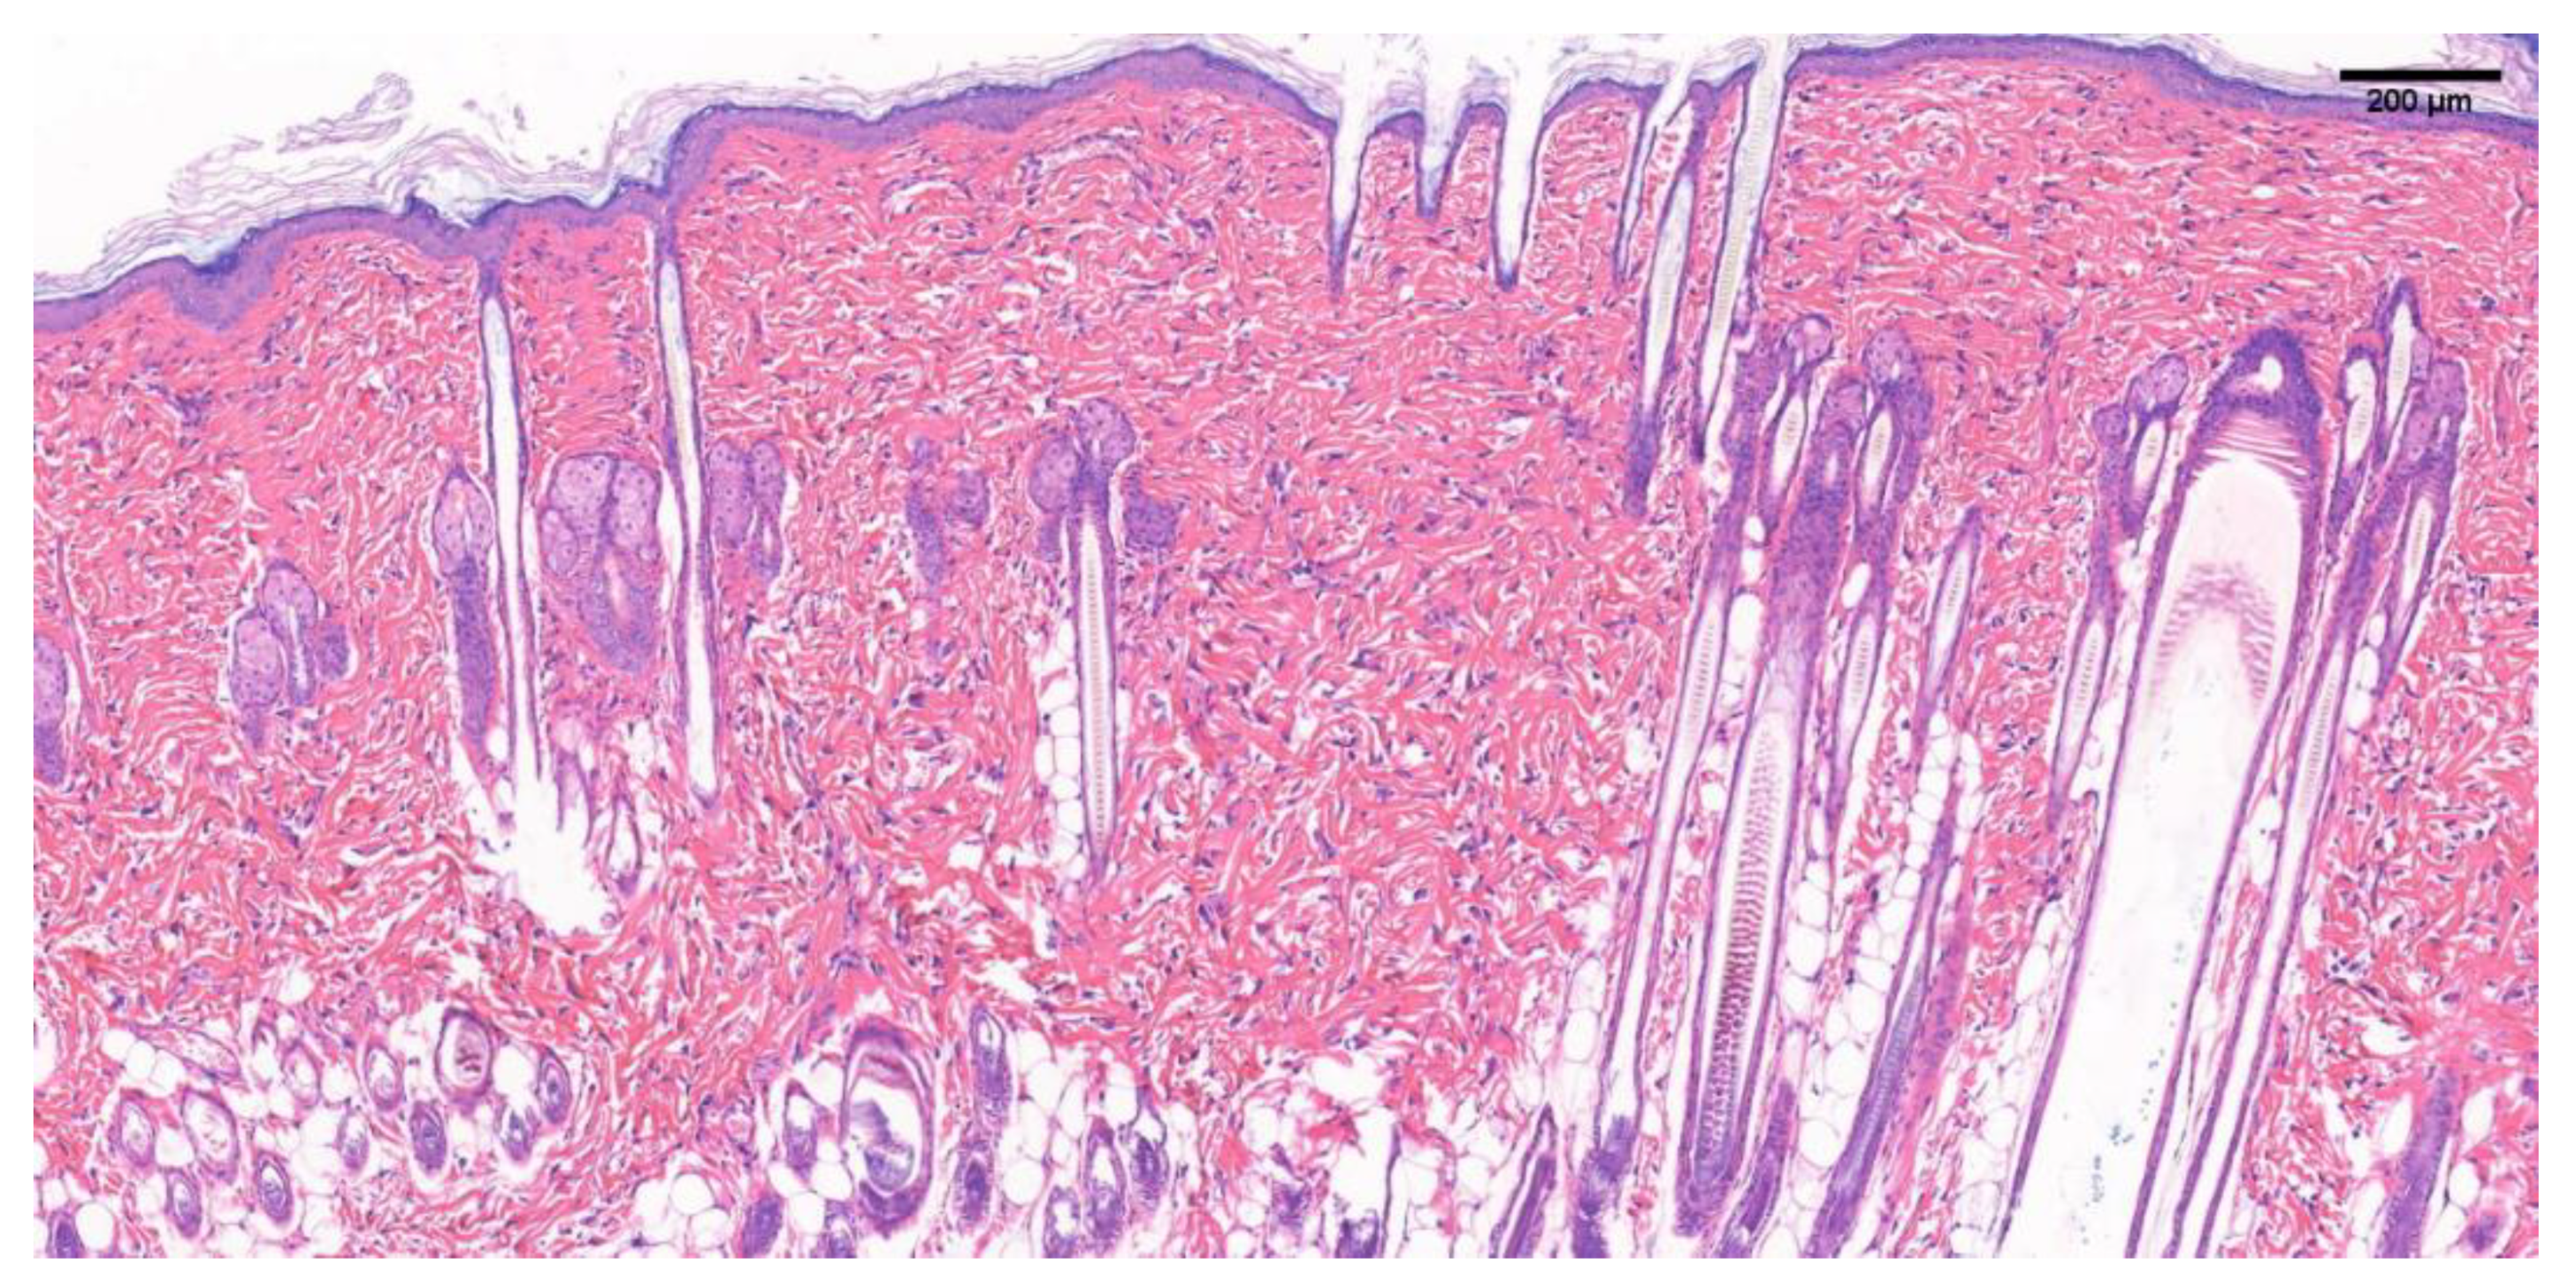

The H&E stained image of 150~200 g SD rat normal skin in Figure 7 shows a normal tissue structure. Normal skin has epidermis, dermis, hair follicles, sebaceous gland appendages, and blood vessels, and dermal tissue contains a large number of fibroblasts and elastin fibers, giving the skin elasticity and ductility.

Figure 7. H&E staining image of normal skin tissue of SD rats. Scale bar = 200 μm.